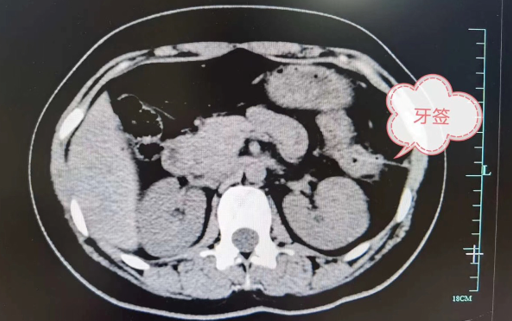

右上:误吞牙签刺破胃壁